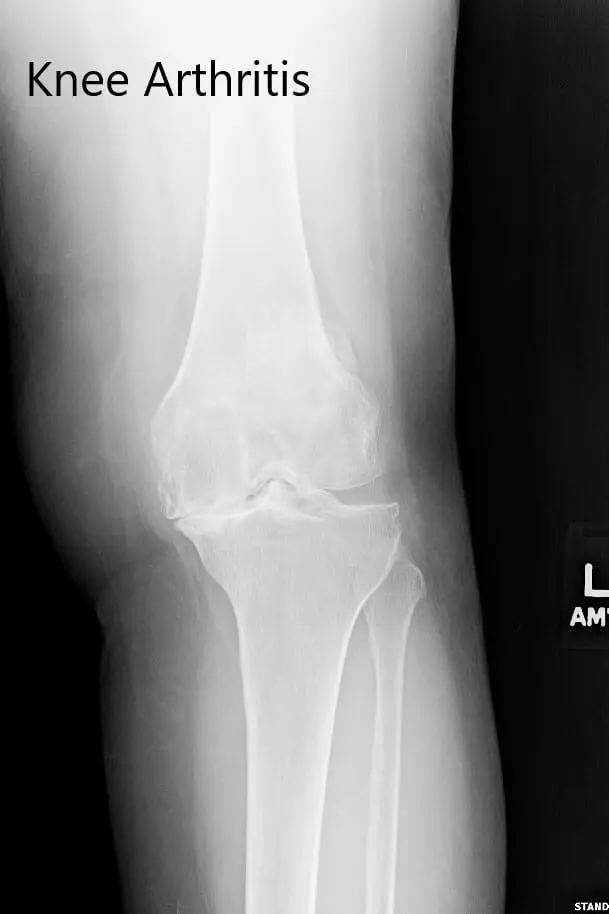

Imaging studies revealed severe bilateral osteoarthritis. The left knee was worse than the right knee. Considering the patient’s lifestyle limiting knee pain, he was advised left total knee replacement. Risks, benefits, and alternatives were discussed at length with the patient and his son. He decided to go ahead with the procedure.

Preoperative X-ray of the left knee showing severe osteoarthritis in anteroposterior and lateral views.